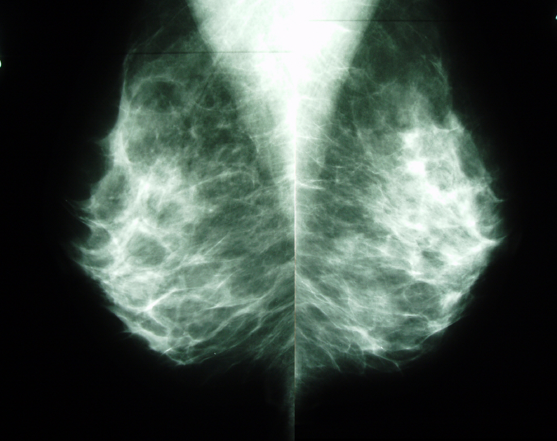

Lors de ma révision des 40 000 mon dernier contrôle annuel, ma gynéco, calculant que j’avais eu 40 ans cette année, m’a rédigé une ordonnance pour une mammographie – alors que je ne présente pas de facteurs de risque particulier tel que parente au premier degré ayant eu un cancer du sein. En France, on recommande de commencer le dépistage à 50 ans, mais je sais que dans d’autres pays comme le Canada, toutes les femmes sont appelées à faire des mammographies à partir de 40 ans. Et parfois, c’est vrai, ces mammographies permettent de repérer et de traiter à temps des cancers qui auraient pu être fatals dépistés plus tard. D’autres fois, elles se contentent de mettre en évidence des kystes bénins ou autres masses vouées à se résorber toutes seules, et la patiente se retrouve donc soumise à des examens et un stress inutiles. Surtout, une mammographie n’est pas un examen anodin dans la mesure où elle diffuse un rayonnement risquant, à terme, de provoquer le genre même de tumeur qu’elle est censée détecter. Mais il est très difficile de mesurer précisément les bénéfices et les coûts de cette procédure, si bien que j’hésite… J’hésite beaucoup.